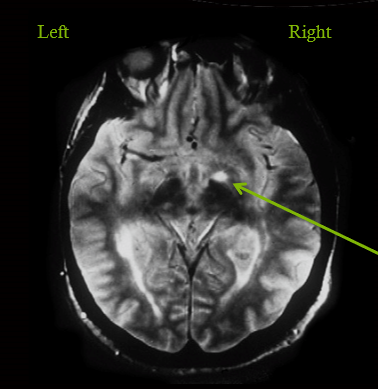

demyelinating plaque that is affecting the optic tract

infarct in MCA territory leading to all loss of fibers losing vision on opposite side